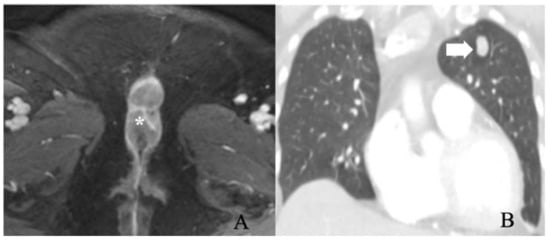

| IVB—Distant metastases |